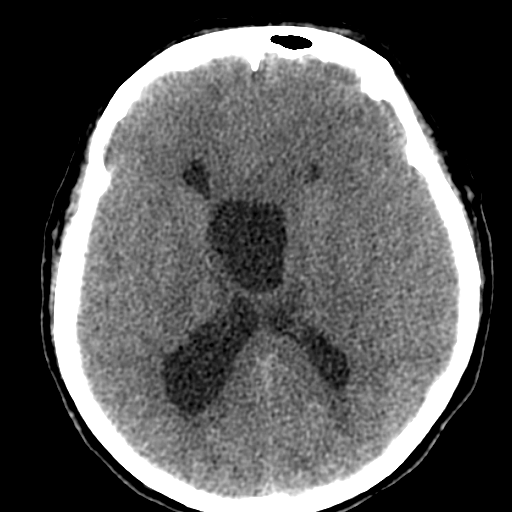

Действительно любопытно! Только сканов мало. Пока мысль о кисте полости межжелудочковой перегородки. Нет ли там где препятствия или изолированная киста?))

Я бы может сказала что здесь агенезия мозолистого тела. Как мне не хватает МРТ данных (. Агенезия ? Перегородки. Сергей Николаевич подскажите возраст пожалуйста. Здесь должна быть выраженная неврологическая клиника. Расскажите побольше о пациенте.

А кисту куда девать? Попадалось заключение КТ "Агенезия мозолистого тела" у пациента с кистой прозрачной перегородки.

Больному около 55 лет, клинику дает не сколько само образование, а компрессия структур мозга, базально вообще беда (отчасти видно компреммию некоторых базальных цистерн мозга). Сразу скажу насчет эпидермоидной кисты - ДВИ не будет :)

Однозначно киста, значит, осталось выяснить какая, холестеатома или арахноидальная?